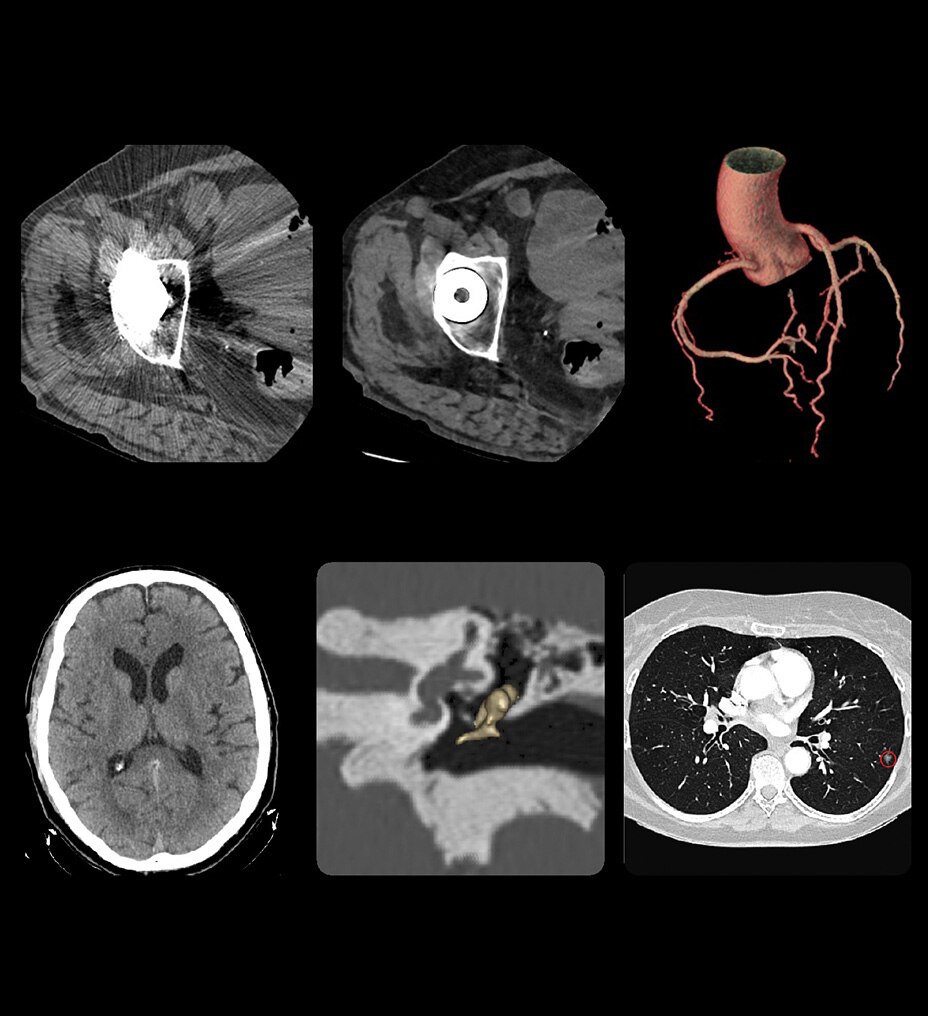

SIGNA™ Champion offre un design modulare con opzioni software e hardware pronte per soddisfare le priorità cliniche. Include strumenti di base e avanzati e soluzioni per la qualità delle immagini come AIR™ Recon DL e Sonic DL™. Queste applicazioni consentono non solo di ottimizzare i casi di routine, ma anche di operare in altri campi specifici come neurologia, apparato muscolo-scheletrico, cardiologia e oncologia. E non è tutto. SIGNA™ Champion è in grado di offrire configurazioni a 32, 48 e 64 canali per garantire la massima flessibilità e semplificare la configurazione delle bobine sulla base delle diverse anatomie.